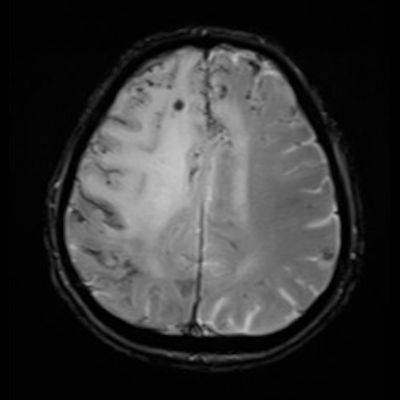

77 Y, E

1 aydır sol kol ve bacakta güçsüzlük, konfüzyon

Enfeksiyon markerları negatif

Serebral Amiloid Anjiyopatiye ile ilişkili inflamasyon (CAA-ri)

Serebral amiloid anjiopati ilişkili inflamasyon